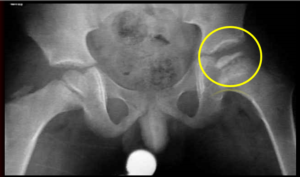

Главным способом диагностики данного заболевания является рентгенография. Используют исследование в стандартных проекциях и проекции Лауэнштейна. Исследование помогает определить степень разрушения и состояние сустава, а также определить стадию патологии.

Также рекомендуют пройти УИИ суставного сочленения и УЗД сустава, определяющую состояние костной и суставных тканей, состояние кровотока и структурные изменения в кости.

Редко для подтверждения диагноза используют исследование МРТ, которое помогает определить наличие отека костного мозга.